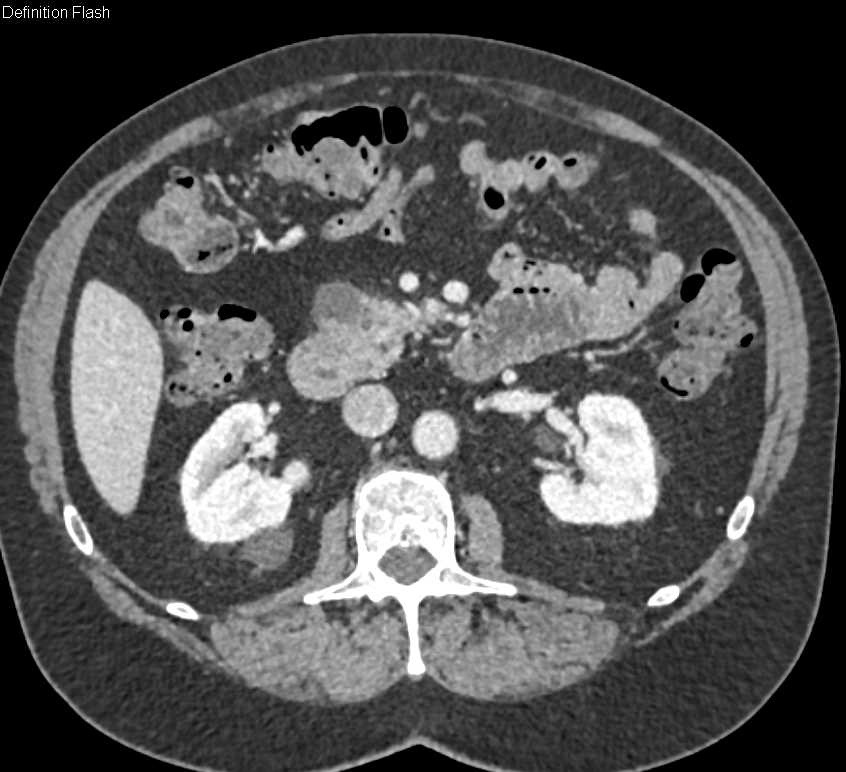

Invasive Adenocarcinoma Head of the Pancreas with Local Spread